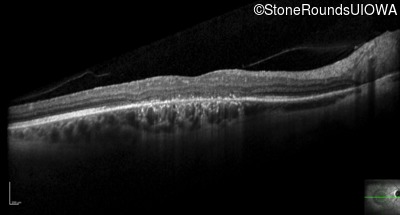

Optical Coherence Tomography - Left - 10/160 sc

Exemplar / OCT Stack